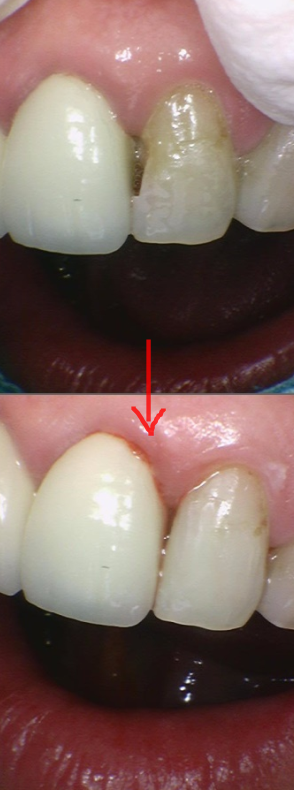

231127

앞니 충치 레진으로 당일 치료를 완료하였습니다.

30분정도면 완료가 되는

간단한 치료랍니다!